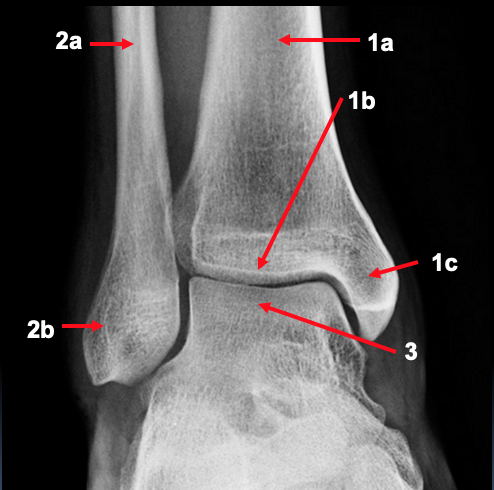

What is shown in the AP right ankle radiograph?

1. tibia

a. distal shaft

b. plafond

c. medial malleolus

2. fibula

b. lateral malleolus

3. talus

What is the name for the articulation between the tibia and fibula?

syndesmosis fibrous joint

it is maintained by the interosseous membrane and the ligaments around the 2 bones

Why may ankle fractures sometimes be called ‘tri-malleolar’?

if there is involvement of the posterior malleolus

this is the region of the tibia which projects distally